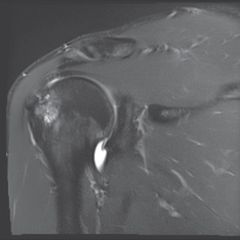

Coronal magnetic resonance arthrography